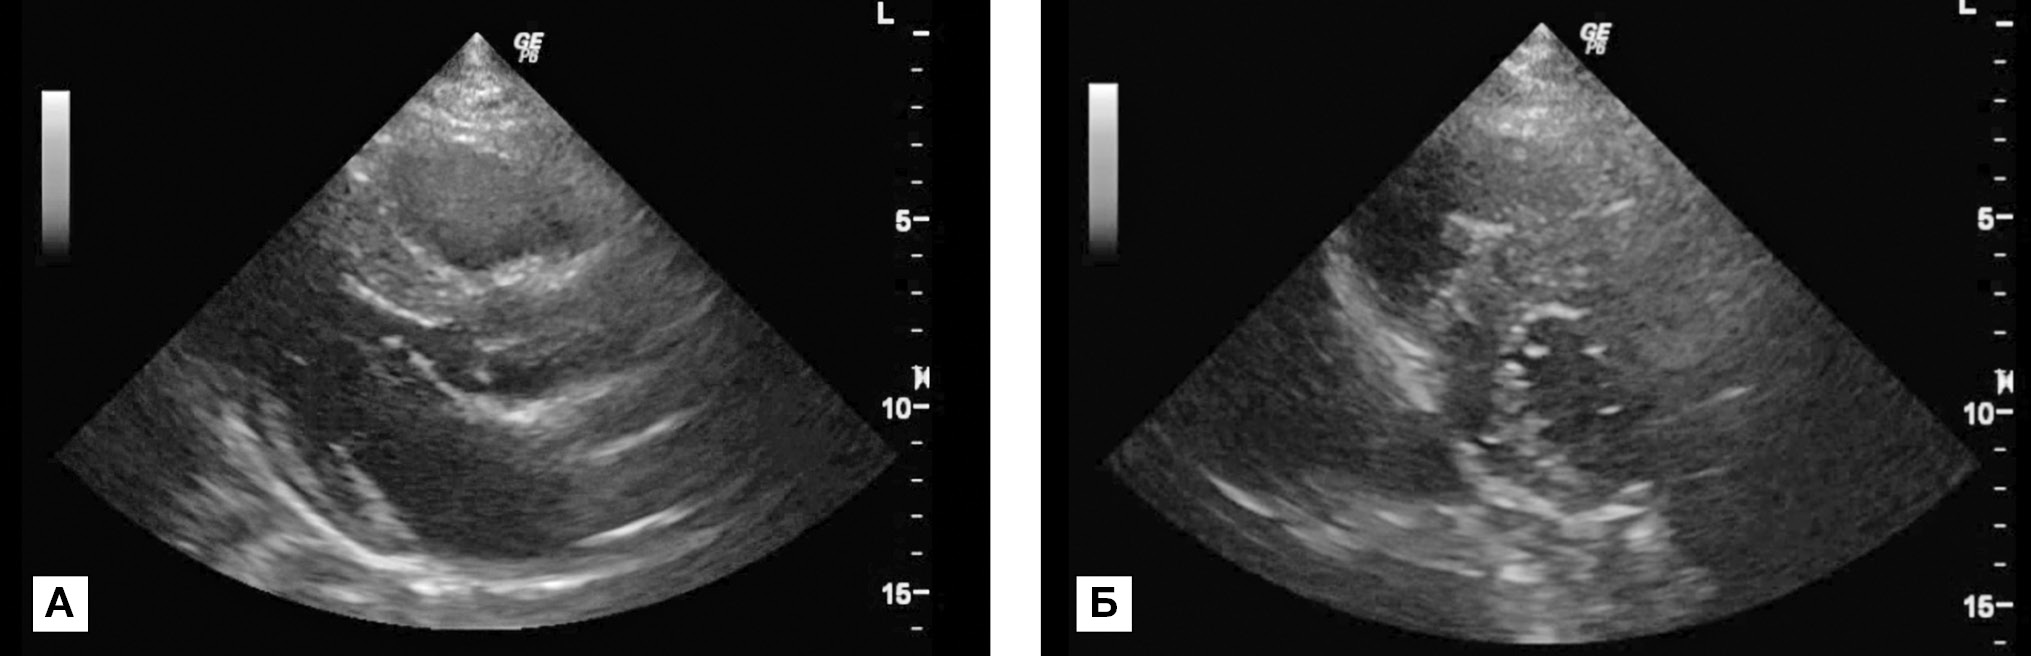

По данным эхокардиографии (ЭхоКГ) от 19.10.2015: межжелудочковая перегородка 1,8–1,9 см, задняя стенка левого желудочка 1,2 см (рис. 1 А, Б). Нарушений локальной сократимости не выявлено, фракция выброса ЛЖ 75%, значительное расширение левого предсердия. Внутрижелудочковый градиент в покое 15/6 мм рт.ст., во время выполнения пробы Вальсальвы 60/27 мм рт.ст., во время физической нагрузки (приседание) 108/54 мм рт.ст.

Рис. 1 А, Б. Эхокардиографическое исследование больного М.